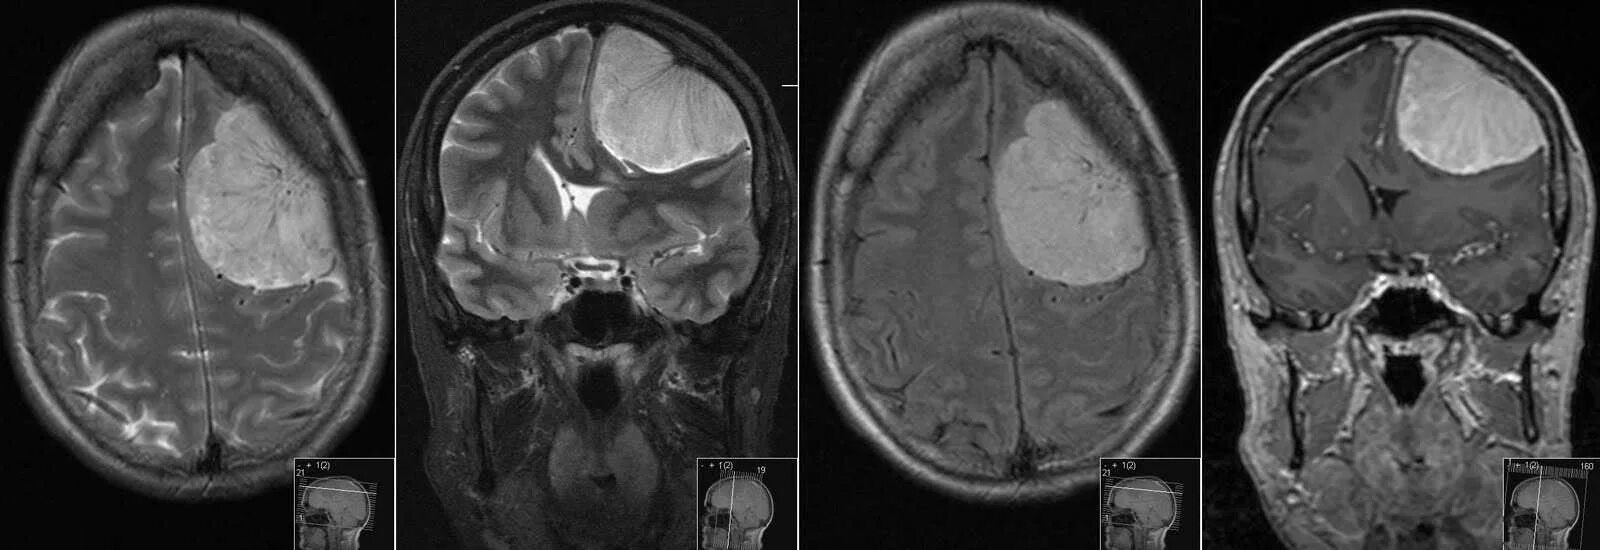

Менингиомы головного мозга мкб